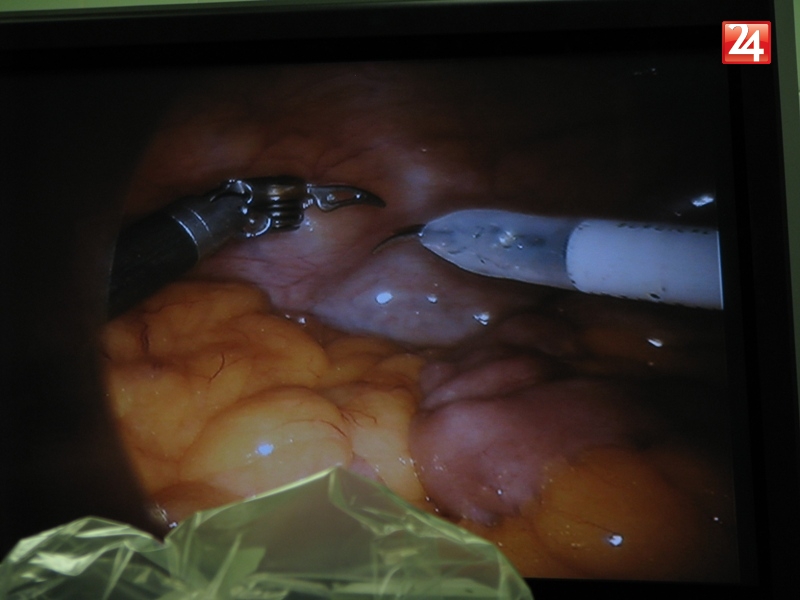

Galéria k článku Rooseveltova nemocnica opäť boduje!